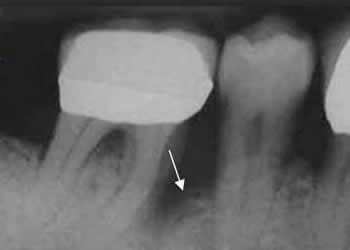

Fig 46. Absceso periapical.

Rx periapical. Disminución de la densidad del hueso alveolar, que rodea las raíces dentales, de bordes mal definidos. Clínicamente hay dolor y cambios inflamatorios de los tejidos blandos, por la formación de absceso. (Flechas gruesas). En otra pieza se identifica caries. (Flecha delgada).